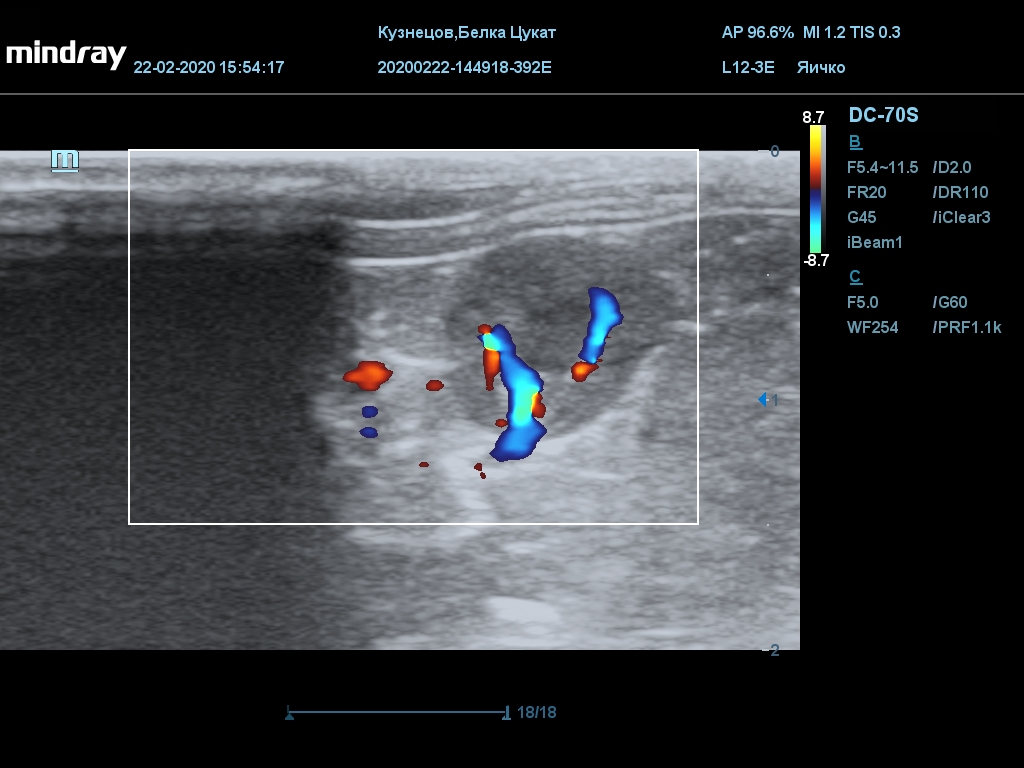

УЗИ

(почки, мочевой пузырь и, предположительно, простата)

Обращаю внимание, что делала УЗИ и писала заключение узист, которая специализируется на кошках и собаках, поэтому она сделала узи и описала, как смогла, но тонкостей грызунячьей анатомии она не знает.

Приложил только фото, есть ещё пара видео, но не знаю, как тут выложить, и надо ли.

Каудальнее мочевого пузыря визуализируется округлая структура размером 11,1 х 8,3 мм с ровными контурами гипоэхогенная однородная, с признаками васкуляризации.

Заключение: УЗпризнаки уролитиаза, объёмная структура каудальнее мочевого пузыря. Признаки расширения левой лоханки.

УЗИ

(почки, мочевой пузырь и, предположительно, простата)

Обращаю внимание, что делала УЗИ и писала заключение узист, которая специализируется на кошках и собаках, поэтому она сделала узи и описала, как смогла, но тонкостей грызунячьей анатомии она не знает.

Каудальнее мочевого пузыря визуализируется округлая структура размером 11,1 х 8,3 мм с ровными контурами гипоэхогенная однородная, с признаками васкуляризации.

Заключение: УЗпризнаки уролитиаза, объёмная структура каудальнее мочевого пузыря. Признаки расширения левой лоханки.